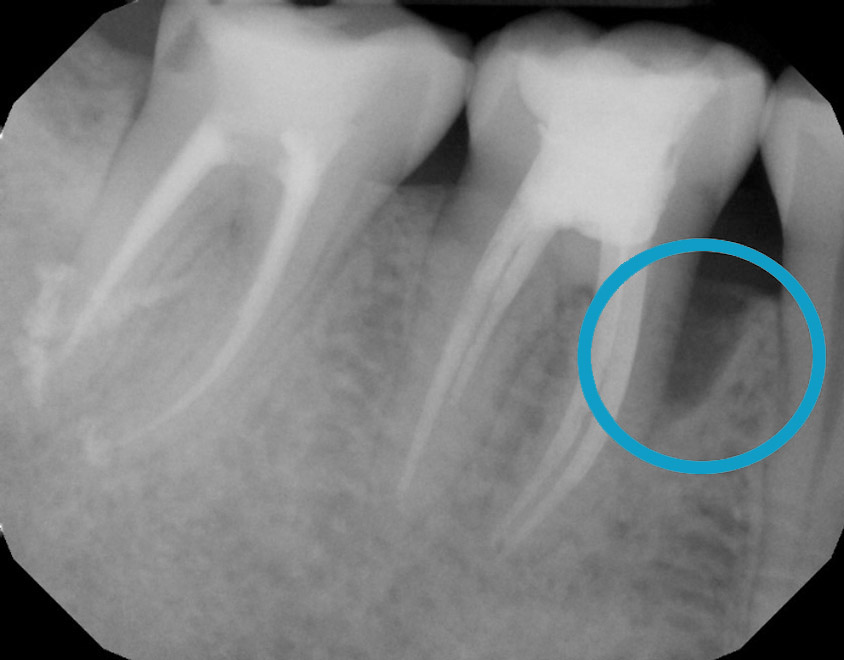

Treat severe gum disease and help the bone grow

One year after treatment, the bone has grown completely to a healthy level. It is all your own natural bone without the need for bone grafting.

Bone healing with ozone treatment and SRP

Reverse Gum Disease: Bone Healing